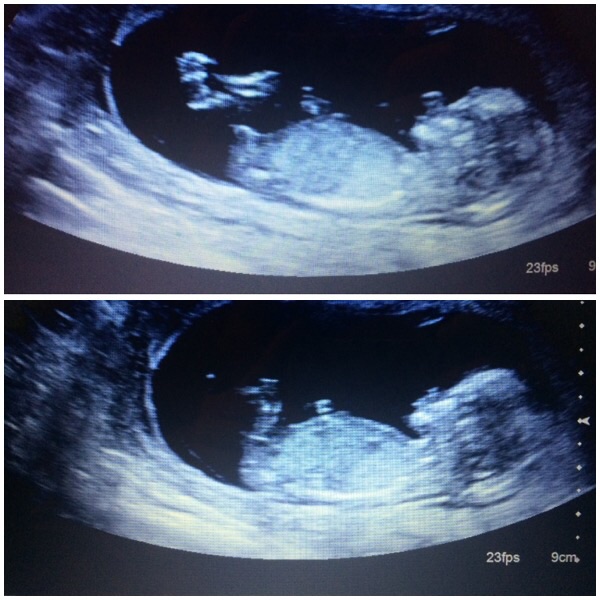

think after my ults that I'm having a boy and it's weird but I think I just know! Although il be happy whatever I'm having long as it's healthy I'm that convinced I've already started buying boys clothes!! What do you think? image

• I'd say boy too. I think I'm team blue going off my scan. already have a boy and the scan is identical, skull shape gives it away.

• I say boy! Skull is flatter but it's only a theory :) hope you get your son!